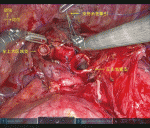

ポート配置:左腕を挙上した右側臥位.da-Vinci Xi (Intuitive Surgical社,Sunnyvale)を使用.1st arm (8-mm,Left hand: Cadiere forceps)– 第6肋間前腋窩線腹側,2nd arm (8-mm,0 degree camera)– 第8肋間中腋窩線上,3rd arm (8-mm,Right hand: Permanent cautery spatula)–第9肋間後腋窩線上,4th arm (8-mm,Retract arm: Fenestrated bipolar forceps)–第7肋間傍椎体,腹側アシスト (12-mm,Access port)– 第8肋間前腋窩線上,背側アシスト (12-mm,Air seal access port)– 第10肋間後腋窩線上.

われわれは術野の固定に際しリトラクトアームを用いている.特に気管支形成術においては,気管支にかけた牽引糸を把持することで固定された良好な術野を得ることが出来る.